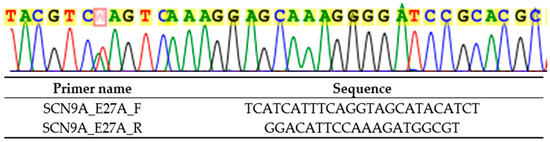

Genetic testing performed in the proband in 2024 revealed a novel heterozygous variant NM_001365536.1 (SCN9A): c.4868T>A p.(Leu1623Gln), by next-generation sequencing with TruSight One clinical exome panel on NextSeq2000 (Illumina Inc., CA, USA), and confirmed on Sanger sequencing (Figure 2). This variant was classified as likely pathogenic by the American College of Medical Genetics and Genomics (ACMG) guidelines: PM1 (located in the highly conserved position in S4 of domain IV where PEPD-causing variants cluster), PM2_Supporting (absent from gnomAD v2.1.1 and v4.1.0), PM5 (different pathogenic missense substitution previously reported at the same residue, p.Leu1623Pro), PP3 (multiple in silico tools predict deleterious effect: REVEL 0.97, AlphaMissense 0.948), and PP4 (phenotype highly specific for SCN9A-related PEPD). The genetic finding is supportive of a genetic diagnosis of the exceedingly rare autosomal dominant SCN9A-related PEPD. Electrophysiological research has shown that the p.Leu1623Pro variant, affecting the same amino acid, depolarized the steady-state inactivation curve, increased ramp current significantly, and shortened recovery from inactivation, all of which are compatible with a gain of function in Nav1.7 [9]. In addition, amitriptyline, which is a non-selective sodium channel blocker, only slightly corrected the steady-state inactivation shift of the mutated channel [9], which may explain the lack of clinical benefit of carbamazepine in both this variant and our detected variant p.(Leu1623Gln). In addition, cooling was reported to be able to improve in the patient with p.Leu1623Pro, which is atypical in PEPD [9].

Figure 2.

Sanger sequencing result (marked in red) and primers used (targeting SCN9A exon 27) for heterozygous NM_001365536.1 (SCN9A): c.4868T>A p.(Leu1623Gln).